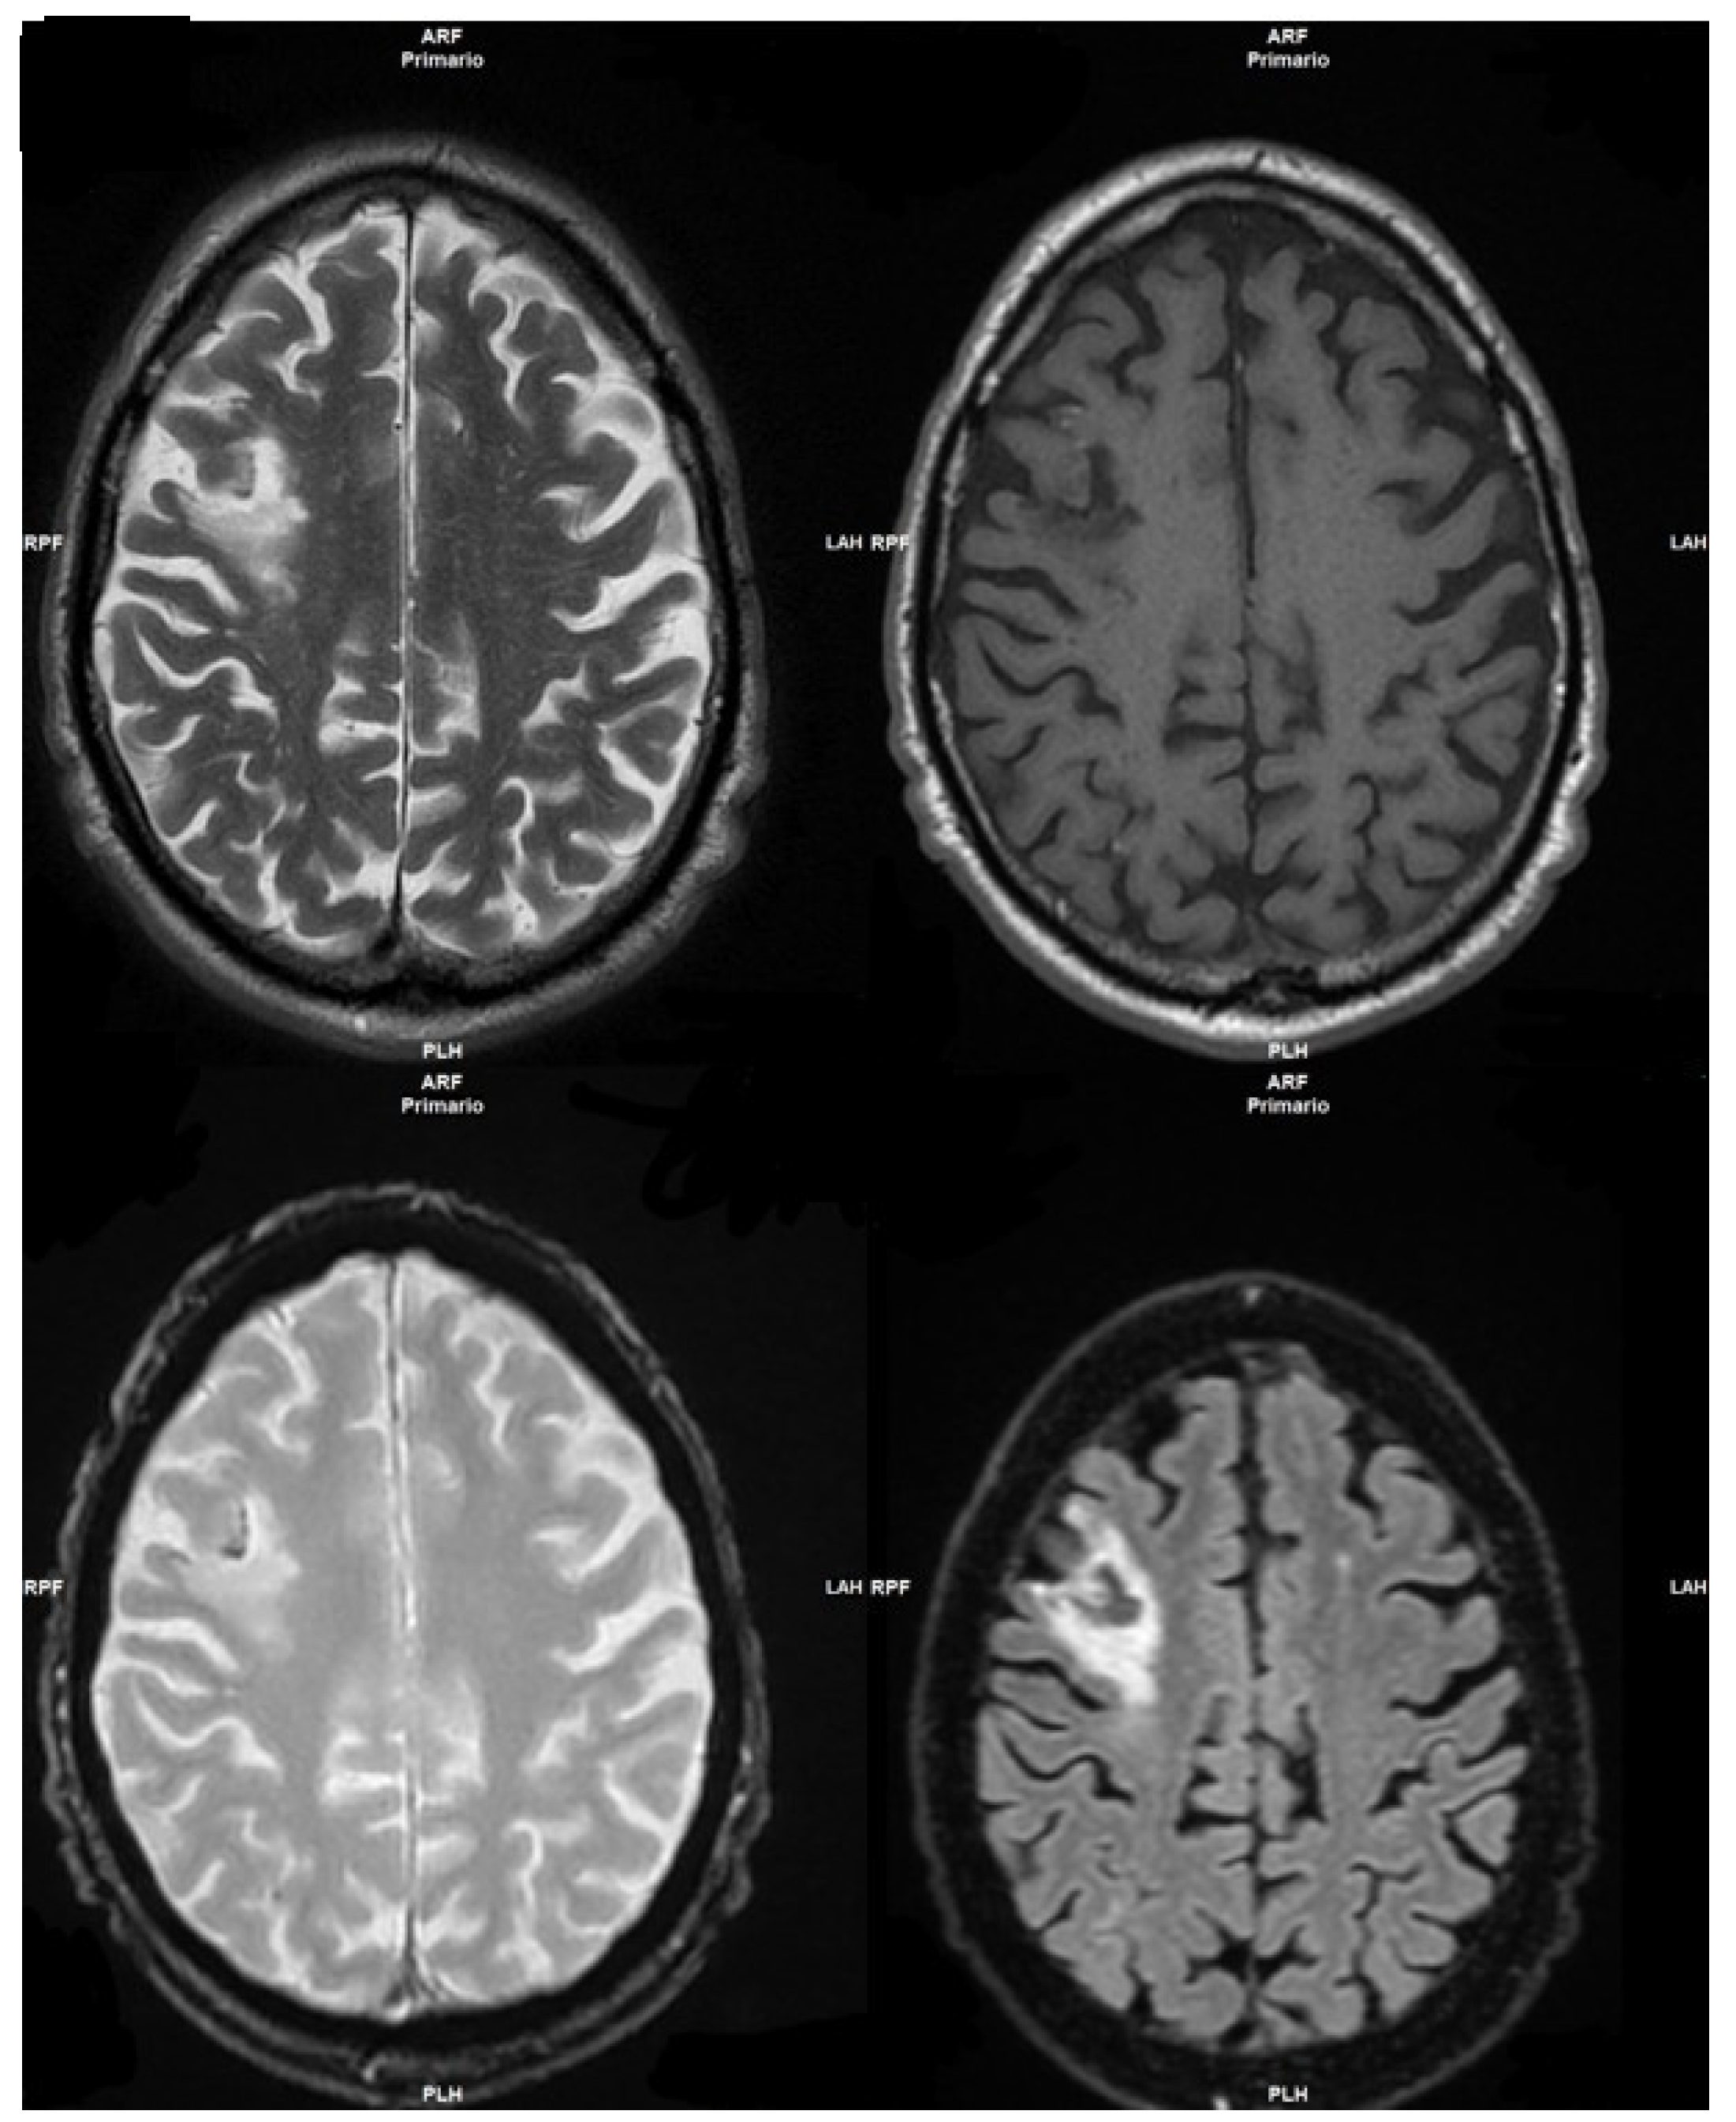

The patient performed a 3Tesla Magnetic Resonance imaging (MRI) examination, which showed an extended hyperintense area in the fronto-temporal-insular left lobe, due to an ischemic attack in the acute/hyperacute phase (Figure 1).

Figure 1. Hyperintense area in the fronto-temporal-insular left lobe.